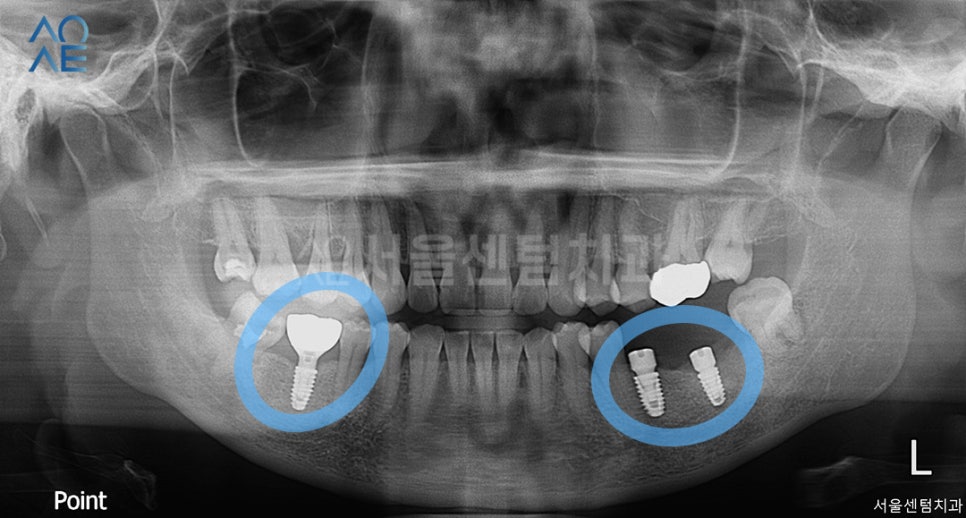

사진에서 우측 상단에 있는 치아에

지르코니아 크라운 치료를 먼저 시작하고나서

임플란트수술을 진행하였습니다.

다행히 무리 없이 잘 식립이 되었고

1주일 뒤 실밥 풀어드리며 경과 체크도 진행했습니다.

첫 식립은 보철물 장착까지 성공적이어서

다음 단계로 왼쪽 아래에도 2개를 식립하였습니다.

(사진 상으로는 오른쪽)

역시나 식립 전에 CT촬영을 하여

위치와 방향을 정밀하게 체크하였습니다.